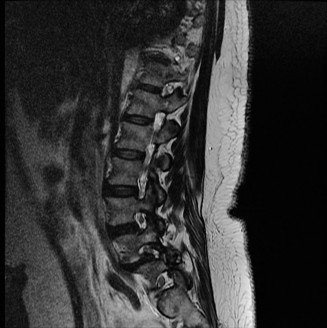

To contextualize the decision-making algorithm, consider the classic presentation of a middle-aged patient with multiple medical comorbidities. A paradigmatic case involves a 48-year-old obese female (Body Mass Index of 43) with poorly controlled diabetes mellitus who presents with severe, unrelenting low back pain, fevers, and chills. Advanced imaging, specifically magnetic resonance imaging (MRI), typically demonstrates discitis involving the L4–5 disc space with adjacent osteomyelitis of the L4 and L5 vertebral bodies. Crucially, in many early or medically responsive cases, there is an absence of epidural abscess formation, and standing radiographs reveal relatively normal sagittal and coronal alignment. When such a patient is neurologically intact—lacking saddle anesthesia, bowel/bladder incontinence, or upper motor neuron signs—the immediate clinical imperative shifts from urgent surgical decompression to aggressive pathogen identification and targeted antimicrobial therapy.

When surgical intervention becomes unavoidable, meticulous pre-operative planning is the cornerstone of a successful outcome. Advanced imaging is non-negotiable. An MRI with and without gadolinium contrast is the gold standard for defining the extent of the epidural abscess, the degree of neural compression, and the involvement of adjacent paraspinal musculature (e.g., psoas abscess). T1-weighted images typically show hypointense signals in the infected marrow, while T2-weighted and STIR sequences reveal hyperintense fluid and edema in the disc space and vertebral bodies. Gadolinium enhancement highlights the vascularized inflammatory phlegmon and the capsule of any abscesses.